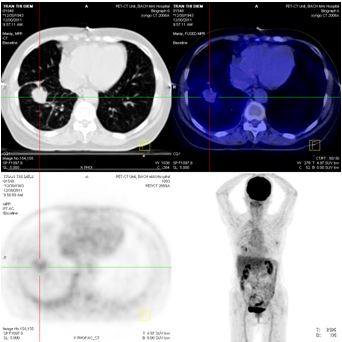

Chụp PET/CT:

Hình 4: Hình ảnh PET/CT có khối u thùy dưới phổi phải 2,6 × 2,8 cm, Max SUV= 5,32

Hình 5: Hình ảnh PET/CT có tổn thương cung sau xương sườn số 5 bên trái, và khối u não vùng đỉnh trái

Chụp PET/CT toàn thân sau 6 tháng điều trị:

Trước điều trị : Khối u thùy dưới phổi phải 2,6 × 2,8 cm, Max SUV = 5,32

Sau điều trị 6 tháng: U tan gần hoàn toàn

Hình 7: Hình ảnh PET/CT toàn thân sau 6 tháng điều trị: Khối u phổi tan hoàn toàn

Trước điều trị: tổn thương thùy đỉnh trái 2 cm

Sau điều trị 6 tháng: tổn thương tan hoàn toàn

Hình 8: Hình ảnh PET/CT toàn thân sau 6 tháng điều trị: Khối u não vùng đỉnh trái tan hoàn toàn.

Trước điều trị: Tổn thương cung sau xương sườn số 5 bên trái